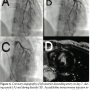

and performed emergent coronary angiography (CAG). CAG showed normal right coronary artery, left circumflex artery, and myocardial bridge at the mid-portion of the left anterior descending artery (Figures 2A and 2B). We had to confirm that the etiology of left ventricular wall motion abnormalities was not due to plaque rupture, but due to myocardial bridging, in order to decide further management. We applied OCT to render a decision. OCT showed smooth internal coronary artery wall at the bridge

and its proximal segment with no evidence of plaque rupture (Figure 3). We considered the possible contribution of coronary artery spasm to the etiology of ventricular fibrillation. We injected nicorandil and diltiazem intracoronarily and started 4 mg/H nicorandil intravenous infusion. Twenty minutes after infusion, the bridge dilated slightly. FFR was also measured by intracoronary adenosine, which was 0.82. We diagnosed the patient with

ventricular fibrillation caused by ST-elevation myocardial infarction (STEMI) due to myocardial bridging and focal spasm, with no clinically significant stenosis in the bridge lesion. We prescribed 200 mg Ca-antagonist, diltiazem, twice a day and 15 mg nicorandil 3 times a day. Clinical course, serial ECG findings, and late gadolinium enhancement MRI at day 5 were compatible with anterior STEMI (Figure 4D). Laboratory data were as follows: cardiac troponin T was 1.6 ng/mL on admission, and the peak serum creatine kinase level and creatine kinase MB isoenzyme were 421 IU/L and 47 IU/L, respectively, 10 H after symptom onset. Repeated coronary angiography at day 7 showed dilatation of the bridge (Figure 4A and 4B). Acetylcholine intracoronary injection induced focal stenosis at the same lesion without any symptoms and ECG changes (Figure 4C). We judged that no clinical ischemia could be induced with the medications. On day 8, the patient was discharged and remains well after 2 years.